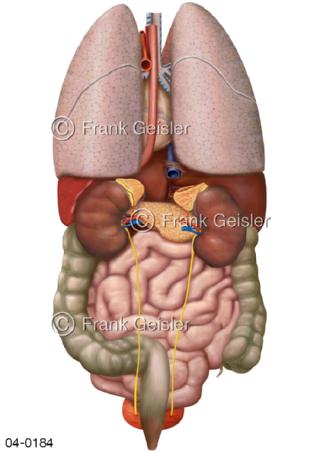

Bildergalerie Topografie Organe

Bilder zur topografischen Anatomie, die Lage der Organe und die Strukturen nach ihren räumlichen Lagebeziehungen zueinander, Übersicht der inneren Organe im Kopf und im Rumpf, Topografie der Organe im Brustraum (Thorax) und im Bauchraum (Abdomen)